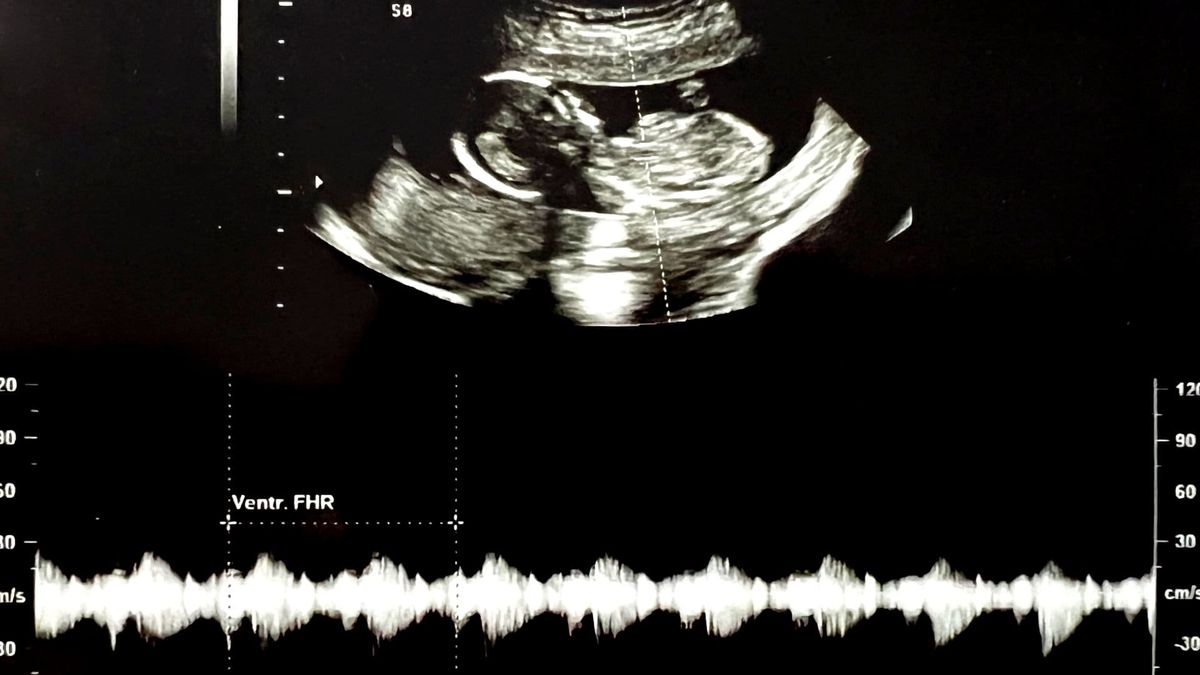

After a traumatic six-month roller coaster through the American medical system we finally discovered that she had a genetic sensitivity to mold. She got treated by an amazing functional medicine doctor and fully recovered, but we still weren't sure if kids were in our future. We had so many questions:

- Can she get pregnant?

- If she gets pregnant will she be able to handle pregnancy?

- If she can handle pregnancy will the baby be healthy?